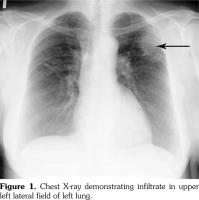

During each subsequent monthly hospitalizations, the patient remained in good general condition, the proteinuria and creatinine serum levels were within normal range. At one of the follow-up visits, nearly one month after the fifth pulse of cyclophosphamide, the patient reported thickening of the right breast, dry cough, and weakness. Chest X-ray demonstrated infiltrative lesion in the upper left lung field (Figure 1). A mild anemia was found, while breast ultrasound confirmed presence of knobby changes in the right breast. Accordingly, the administration of the next cyclophosphamide pulse was postponed and the patient was referred for oncologic consultation. Within the oncology clinic, a needle biopsy of the breast lesion was performed, revealing no neoplastic cells and the histopathological image corresponding to infiltration in the course of granulomatosis with polyangiitis gathering mainly around small size blood vessels (Figure 2). On the basis of infiltrative changes in the lungs, the result of breast biopsy, and presence of anti-neutrophil cytoplasmic antibodies, the recurrence of the underlying disease was diagnosed. Accordingly, the prednisone dose was increased to 1 mg/kg with subsequent tapering to 15 mg/day. Thus a gradual decrease in C-reactive protein levels with improvement of the patient's condition was observed. After a few days, a pulse of intravenous cyclophosphamide (1000 mg) was administered. Following intensification of immunosuppressive therapy, patient’s condition improved, and normalization of serum C-reactive protein was noted. Following five weeks, a control chest X-ray demonstrated no lung infiltrations. Since then, two pulses of cyclophosphamide (1000 mg each, four weeks apart) were given and the treatment with azathioprine, 100 mg per day, has been started. Currently, the patient remains in complete remission.